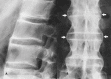

Signs of Nature in Spine Radiology

As medical science developed over time, we have relied on natural imagery to help us recognise and remember things. In this review article, we will be discussing some radiological signs named because of their resemblance to the occurrences in the natural world.